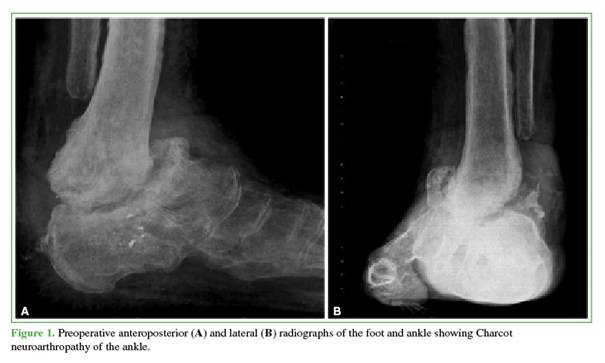

Three patients required revision arthrodesis: one due to implant failure following a fall and two due to nonunion (Figures 1 and 2). Revision procedures involved implant removal, debridement of the arthrodesis site, and re-arthrodesis using a new nail. All revision surgeries were preceded by optimization of metabolic parameters and comorbidities.

At the end of follow-up, seven patients had achieved stable healing of the TTC arthrodesis (Figures 3 and 4). Two developed fibrous healing, which allowed ambulation with orthotic support. One patient required a delayed revision and remains under follow-up. The median time to radiographic healing was 8.6 months (IQR 25-75%: 4.7–8.6).